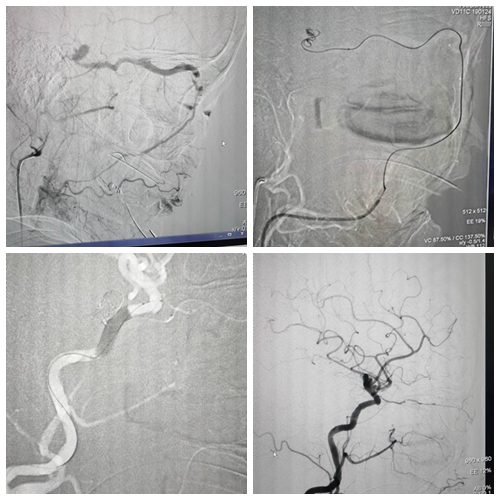

8月17日,湘雅三医院神经外科介入团队完成院内首例采用静脉入路独立完成硬脑膜海绵窦瘘的根治性栓塞。

医院神经外科脑血管团队综合分析病情后认为。目前患者诊断为颈外动脉海绵窦瘘,向眼上静脉引流,引起右眼红肿,搏动性突眼。供血动脉复杂,呈烟雾状,动脉入路无法根治。考虑改用股静脉-颈外静脉-面静脉-内眦静脉-眼上静脉-海绵窦瘘口进行根治性栓塞。静脉入路相对动脉入路,路途弯曲狭窄,难度大,一般很少选择。硬脑膜动静脉瘘是脑血管病介入治疗的难点。

既是困难,也是挑战。团队决定迎难而上,在进行了充分的术前准备评估之后,团队制定了周密的手术方案,在全麻下为患者实行了“颈外动脉海绵窦栓塞术”,耗时4小时完成手术。手术顺利,术后当天右眼红肿明显好转,术后6天患者顺利出院。出院时神清语利,眼部症状已明显好转。